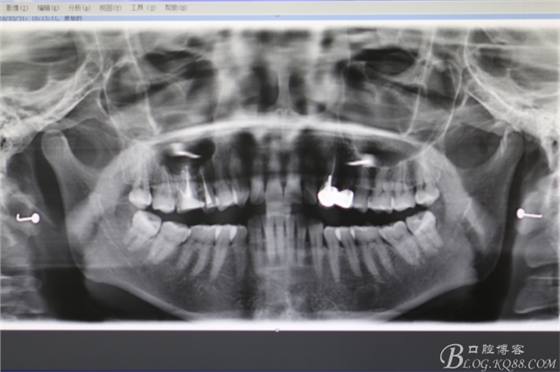

圖4.全景片影像檢查:以16為中心的橢圓形陰影,當時15未作根管治療。